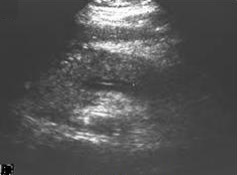

Ultrasound

Abdominal ultrasonography of acute pancreatitis

On abdominal ultrasonography, the finding of a hypoechoic and bulky pancreas is regarded as diagnostic of acute pancreatitis.[citation needed]